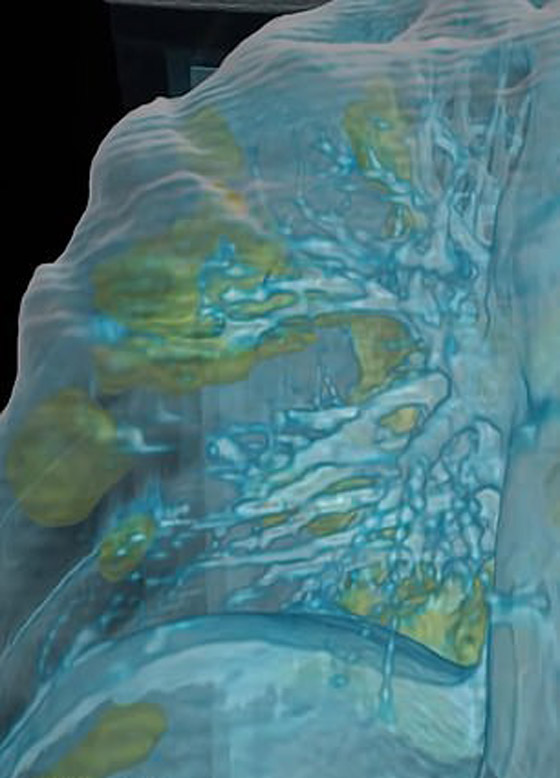

تصوير مقطعي محوسب من مستشفى جامعة جورج واشنطن يُظهر آثار فيروس كورونا المستجد، أو ما يُعرف بـ"كوفيد-19"  رئتي رجل عمره 59 عاماً. فشاهدوا معنا في الفيديو المدهش أدناه كيف تبدو رئة مصاب بفيروس كورونا (فيروس كوفيد 19) وما يحصل داخلها..